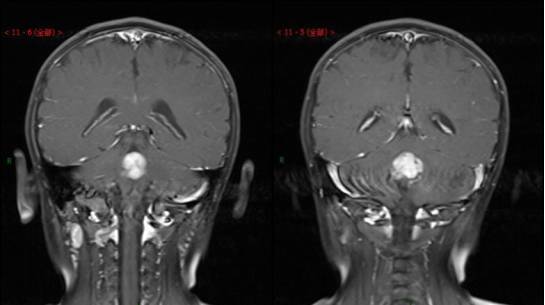

这场悲剧的根源在于妻子姜梅被诊断出患有梅毒和HIV抗体阳性。早在2016年7月,姜梅怀孕数周到宜宾市妇幼保健院建卡时,就已查出梅毒和HIV待确诊。血液检验报告单一直未送达家属手中,直到临产入院才发现缺失。更令人震惊的是,医生在剖腹产术前发现缺失的检验单后,并未及时告知其血液问题。

医院出具的资料显示,新生婴儿艾滋感染待确定。面对女儿的未来,费小华心如止水。他和妻子的感情历程原本是一段美好的旅程,如今却因这场意外变得支离破碎。他并未放弃,而是选择坚持下去。他知道这场斗争漫长而艰难,但为了女儿的未来,他必须为女儿讨回公道。他的心情沉痛而坚定,如同磐石般不可动摇。他将继续奔波于各大医院和相关部门,直到为女儿讨回一个公道为止。